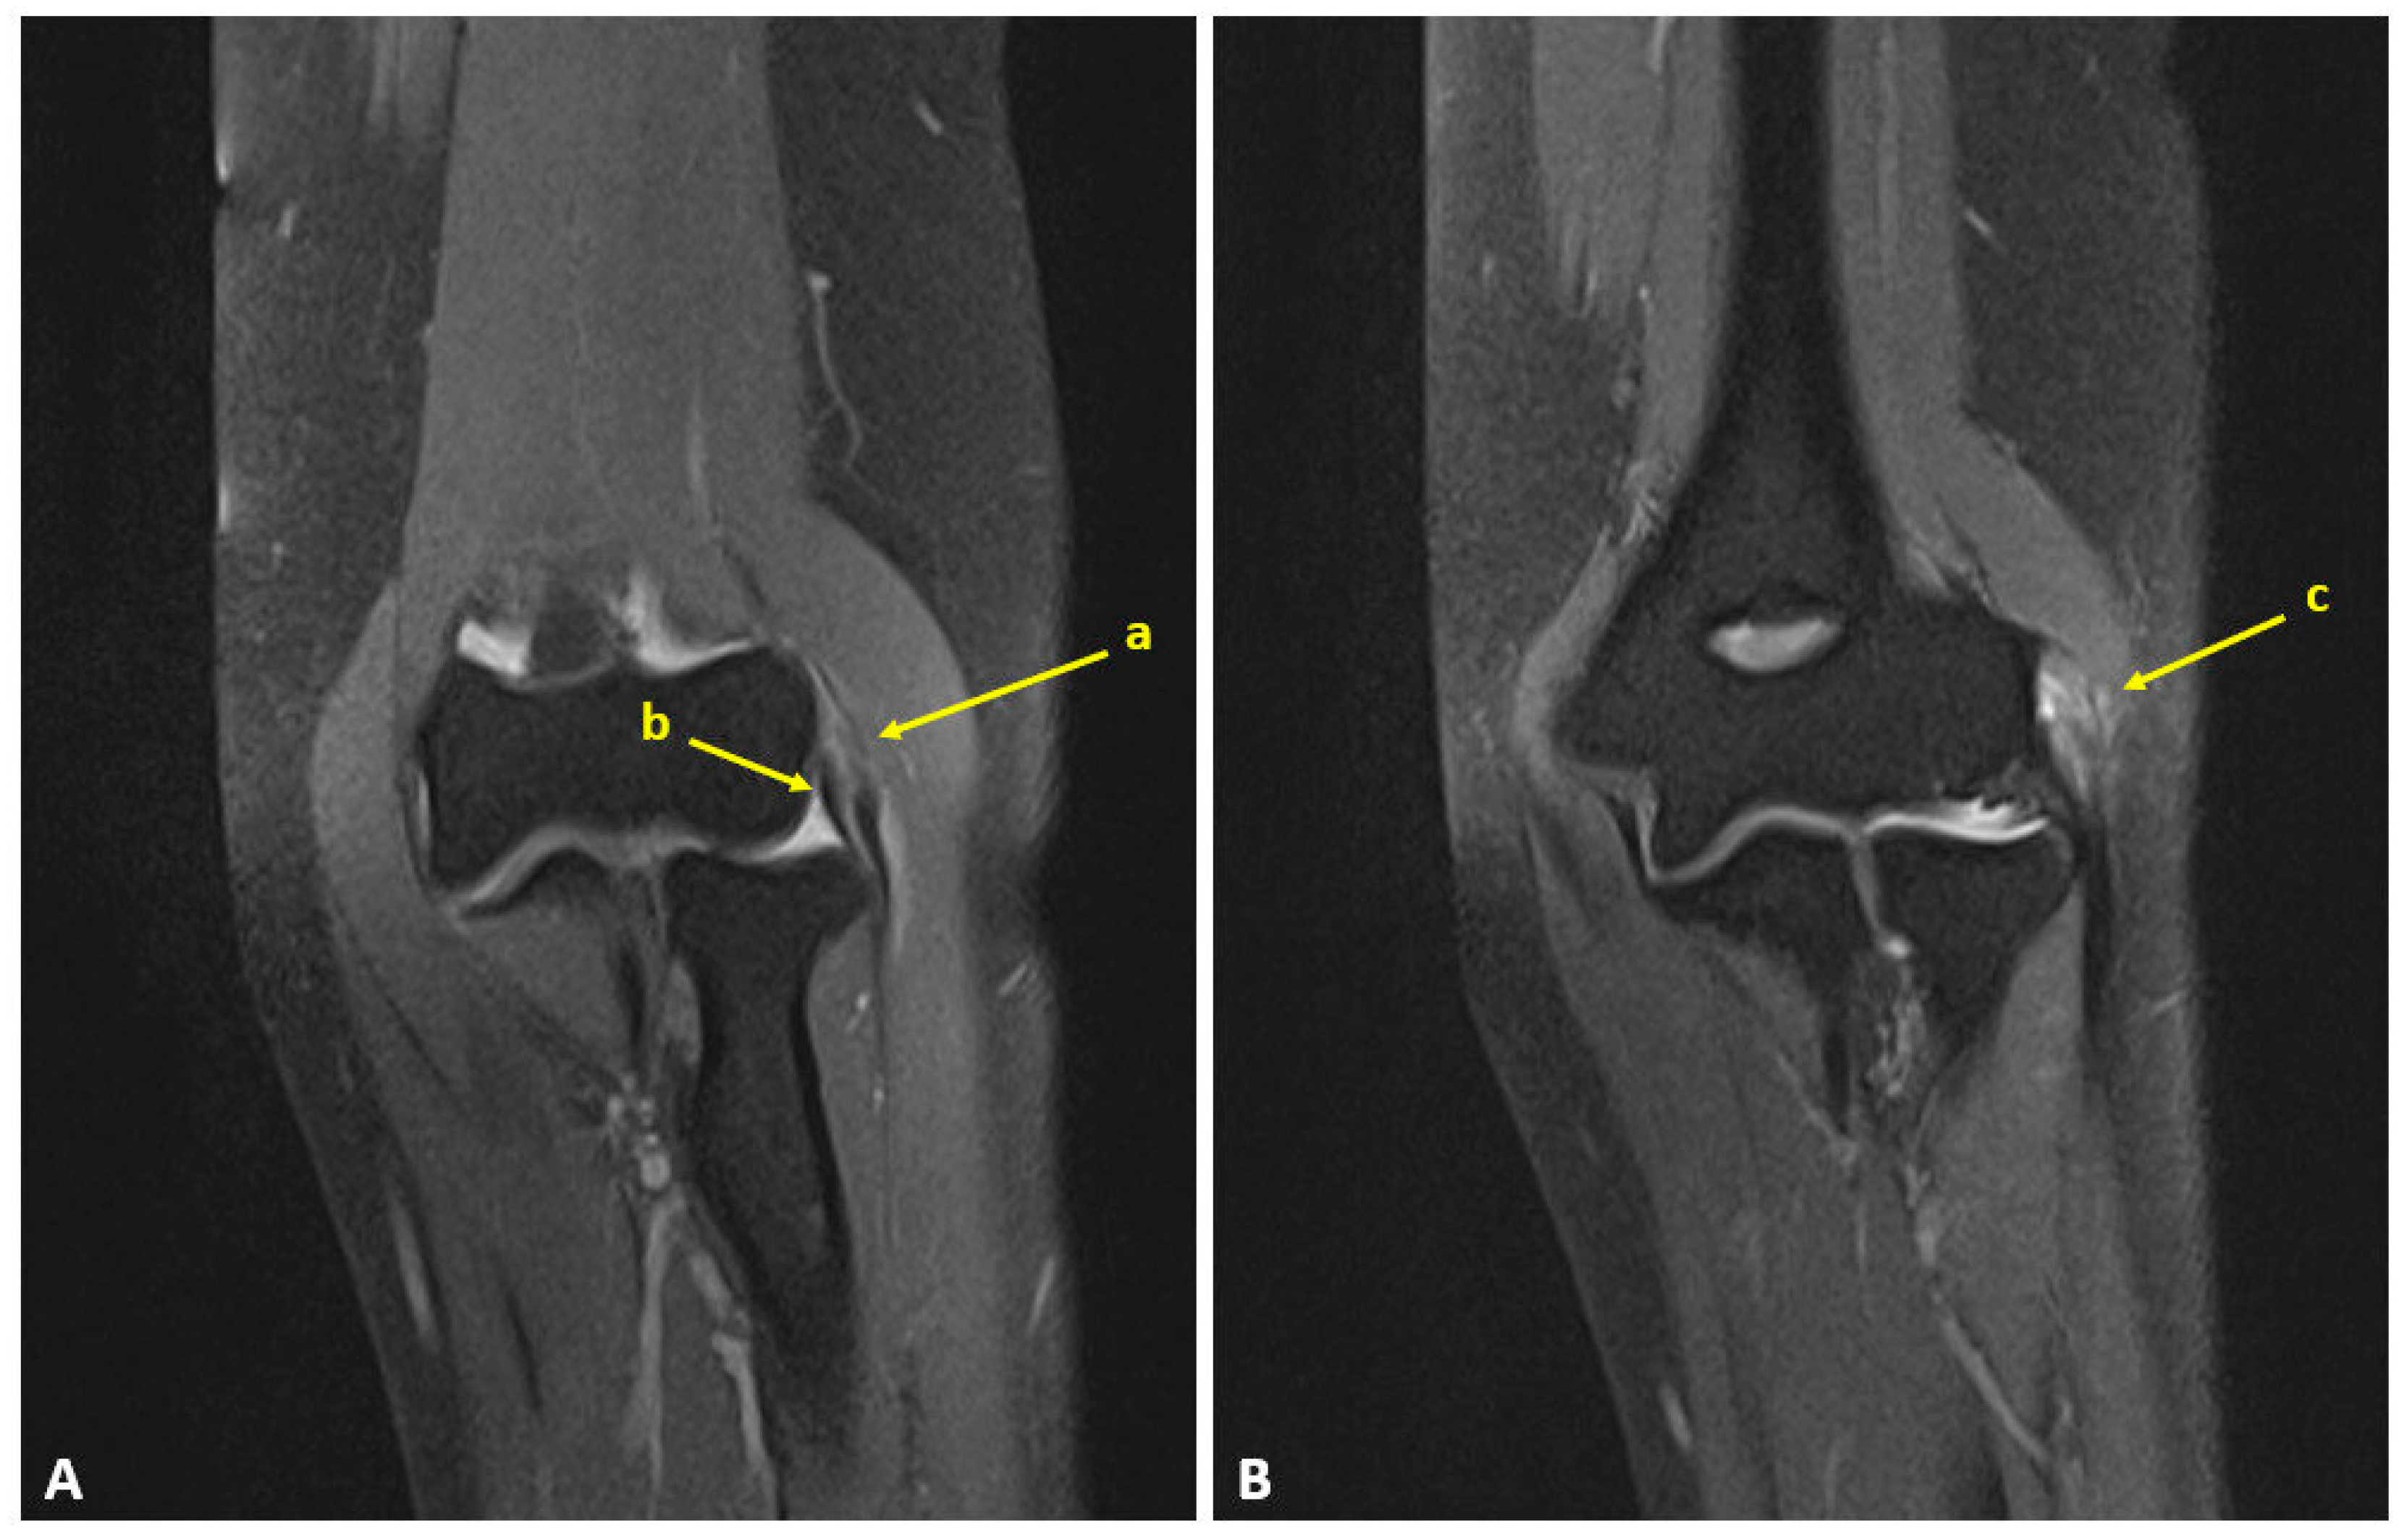

2.2. Surgical Technique